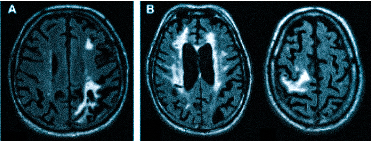

Множественные ишемические очаги при сосудистой деменции на МРТ: отсутствие памяти на недавние события и неадекватное поведение не являются признаками старости, своевременная диагностика деменции и патогенетическая терапия помогут замедлить прогрессирование болезни

демиелинизацию при рассеянном склерозе и иных атрофических процессах;

острые (ишемический или геморрагический инсульт) и хронические нарушения мозгового кровообращения.